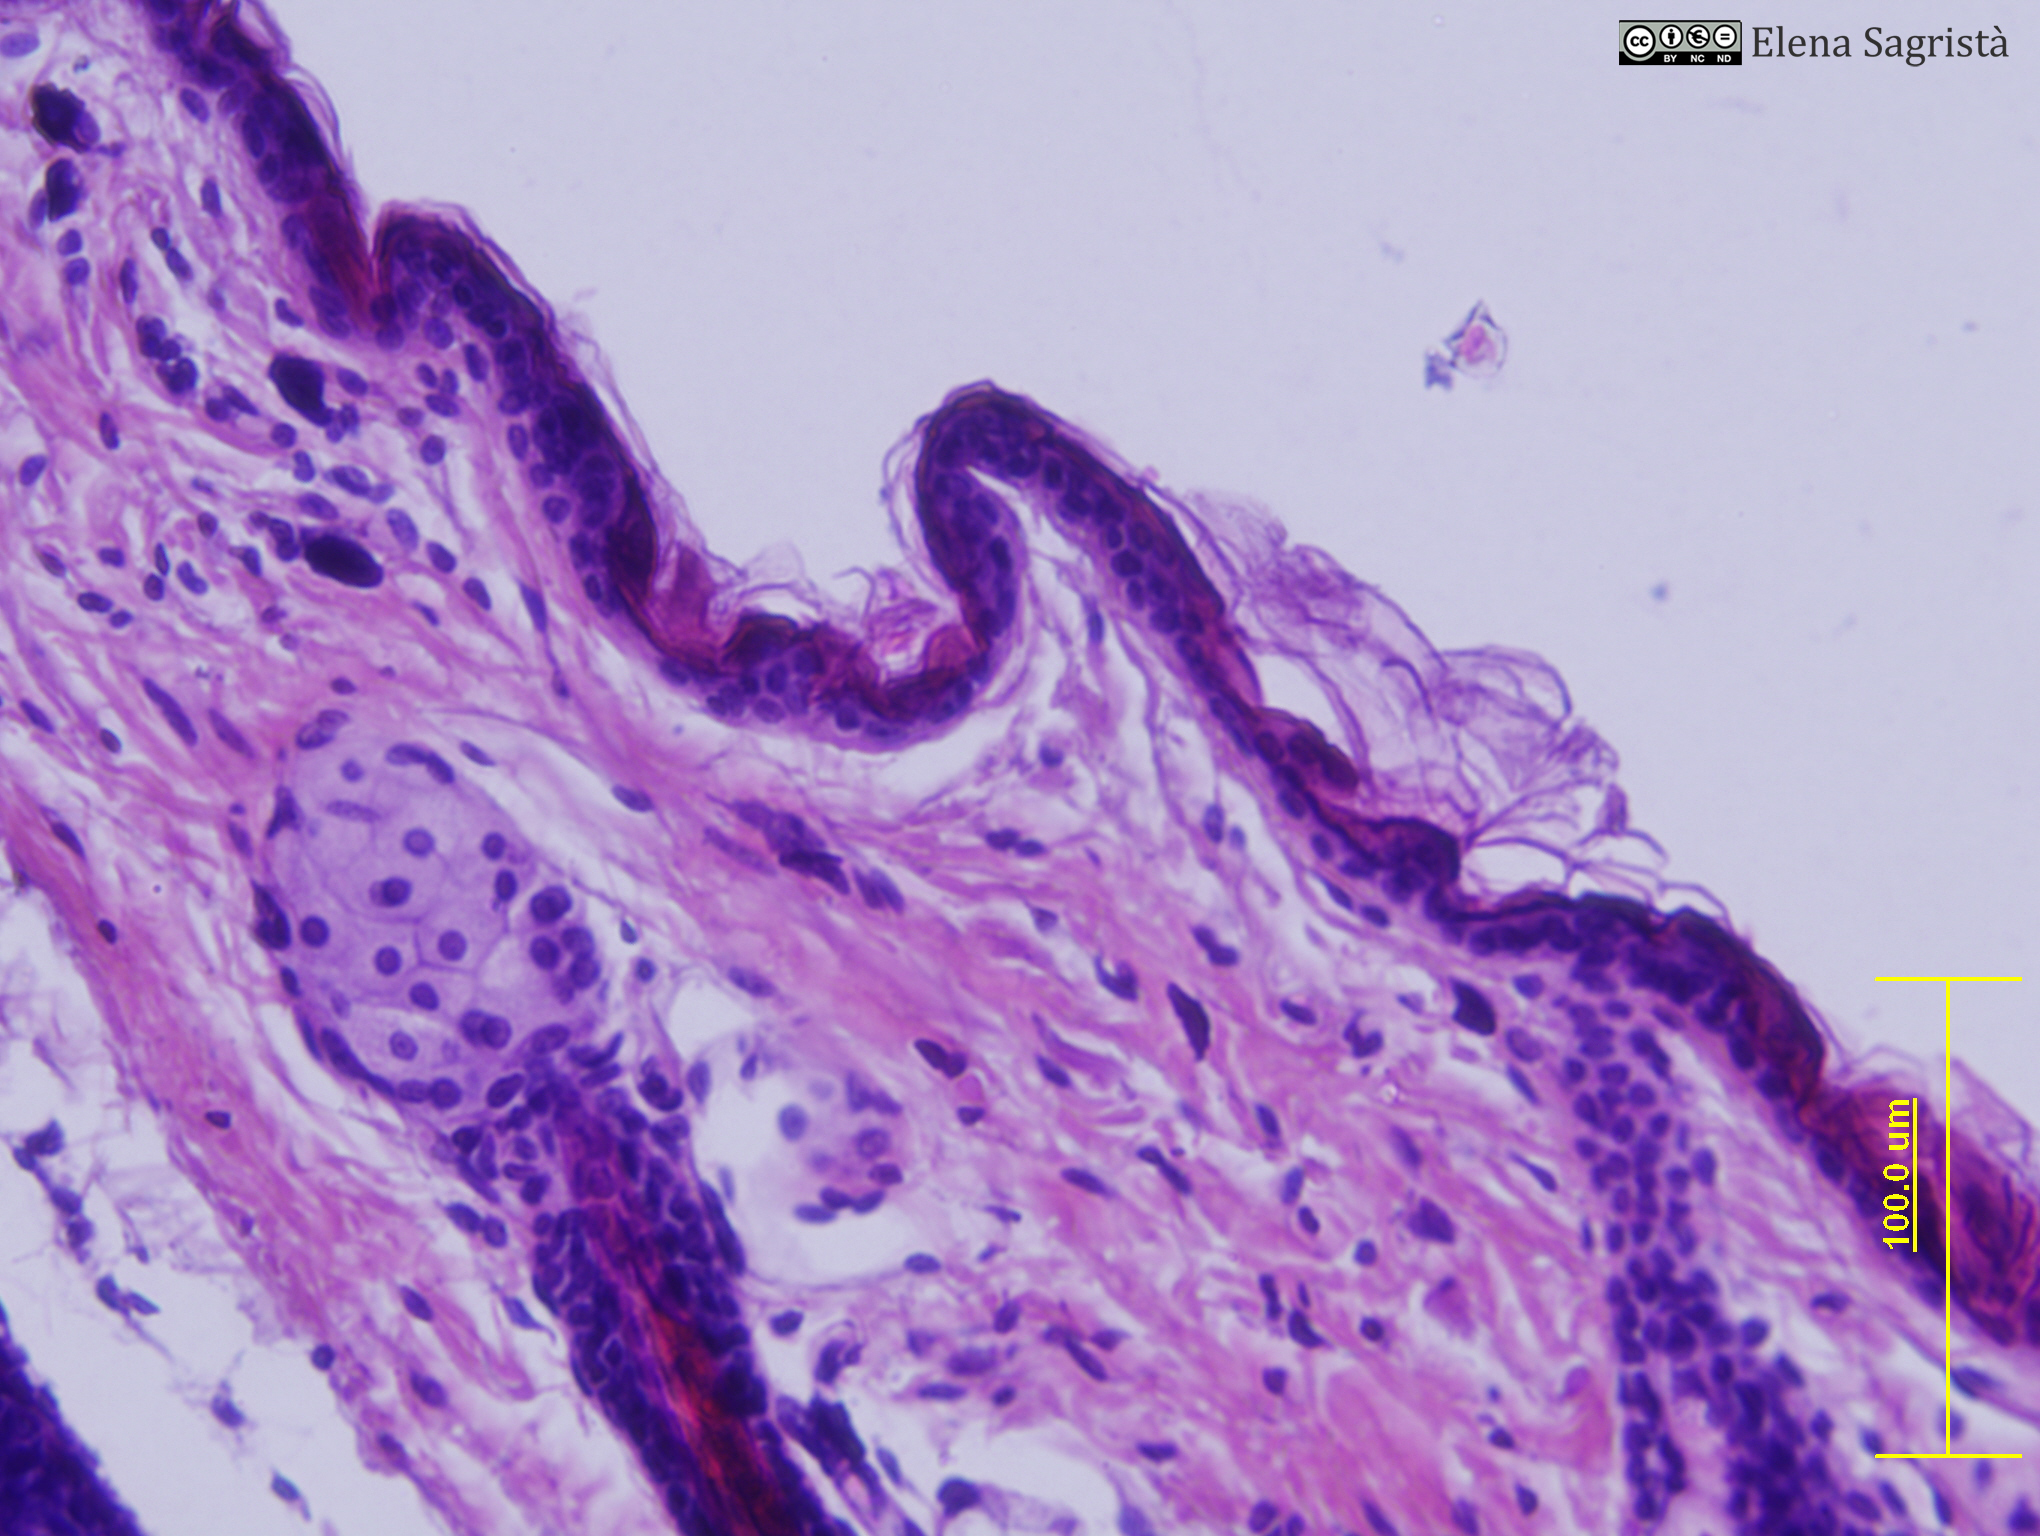

Histologia imatges: 11 Pell

Imatges de preparacions histològiques de Pell. Microscopia òptica.